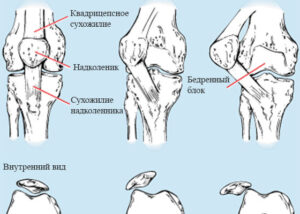

Растяжение колена

Коленный связочный аппарат помогает выдерживать повышенную нагрузку на сустав, действуя как амортизатор. С помощью связок человек может поддерживать не только свой вес, но и свой вес сверху. Растяжение колена провоцируют большие нагрузки на сустав, вызывающие резкую и сковывающую боль. Продолжительность реабилитации будет зависеть от причины травмы, степени травмы и скорости оказания помощи. Что вызывает растяжение …